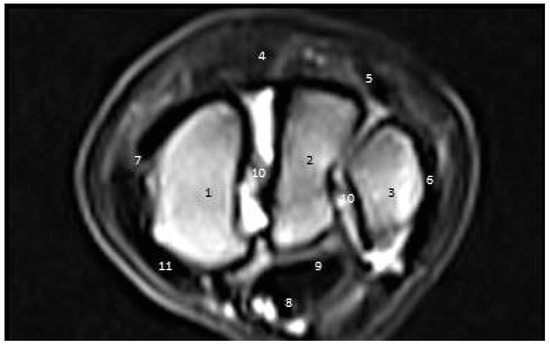

3.3. MRI Findings

3.3.1. First Zone

3.3.2. Second Zone

3.3.3. Third Zone